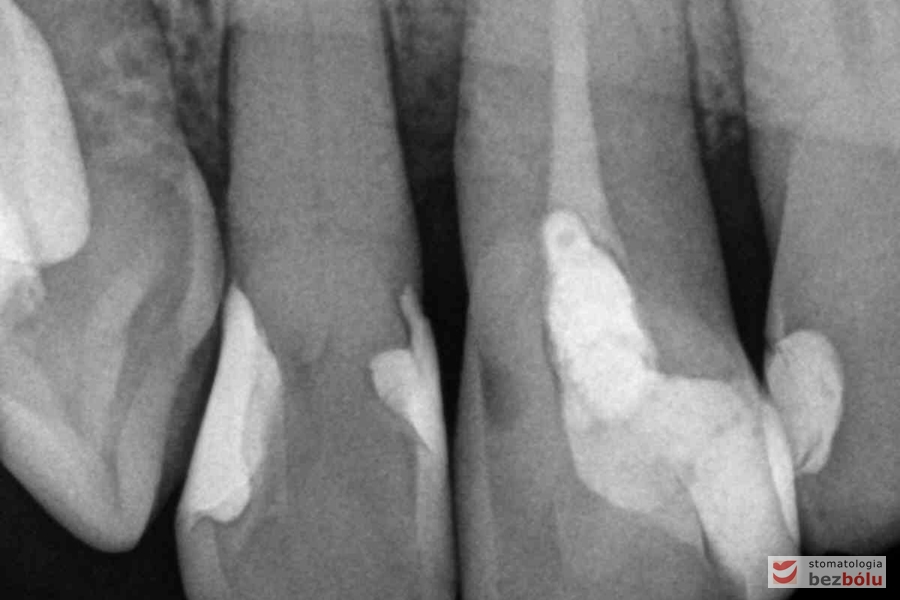

Radiowizjografia - jedynka górna prawa z niedopełnionym kanałem korzeniowym

Radiowizjografia – jedynka górna prawa z niedopełnionym kanałem korzeniowym

Radiowizjografia - szóstka, piątka, czwórka prawa w szczęce, wszystkie kanały niedopełnione

Radiowizjografia – szóstka, piątka, czwórka prawa w szczęce, wszystkie kanały niedopełnione